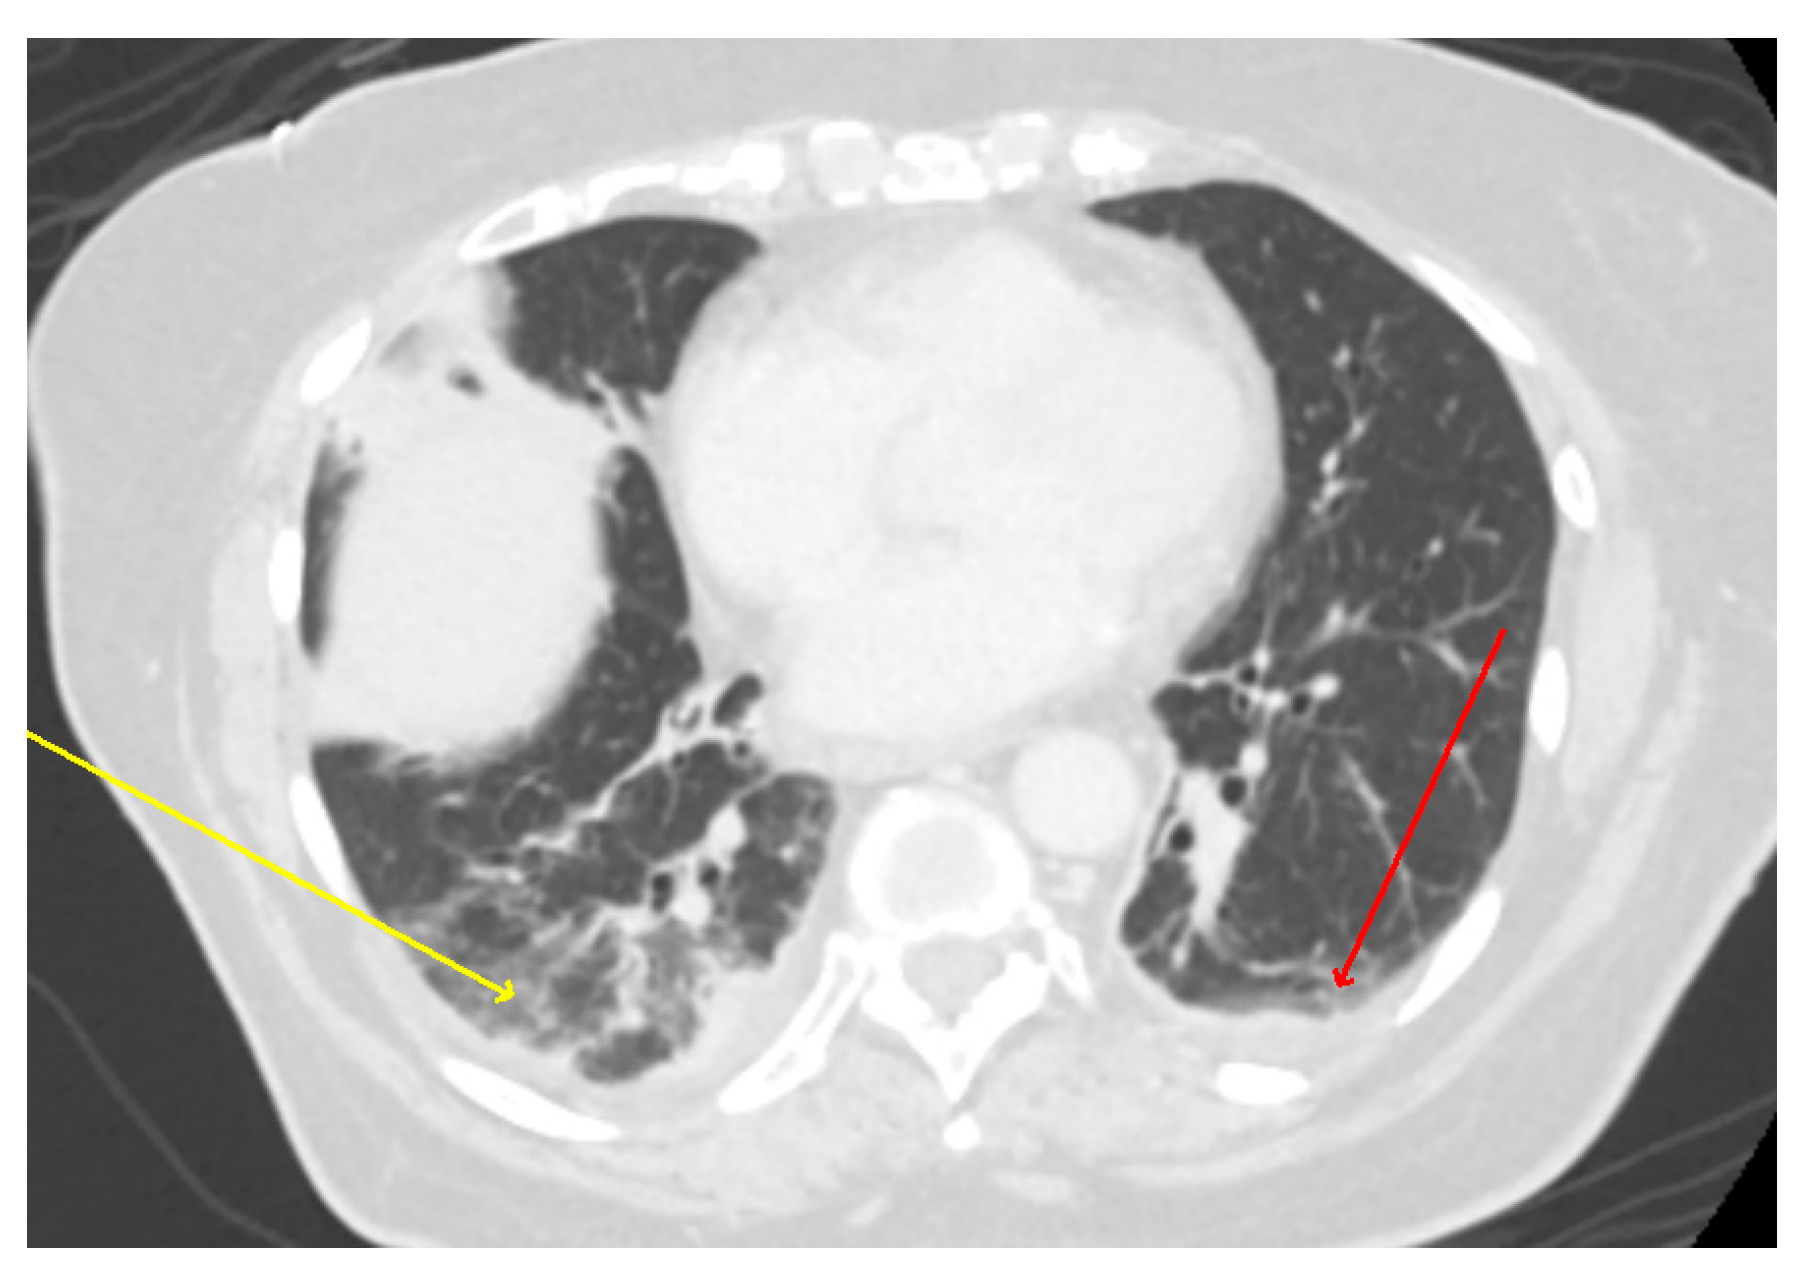

An ultrasound of the gallbladder and biliary ducts did not show any abnormality. A chest X-ray (CXR) demonstrated patchy bibasilar opacities, which were concerning for pneumonia (Figure 1). Computerized tomography (CT) scan of the abdomen and pelvis with contrast did not show any acute intraabdominal abnormalities but demonstrated trace bilateral pleural effusions with bibasilar ground glass opacities which were more severe within the right lung (Figure 2).

Figure 2.

CT scan: CT abdomen showing lower lung fields with bibasilar ground-glass opacities; right (yellow arrow) greater than left (red arrow) with small bilateral pleural effusions versus atelectasis.